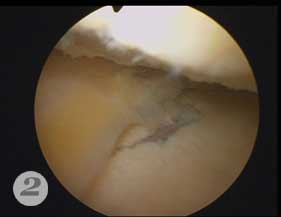

Пример №4 Магнитная томография (МРТ) помогает произвести диагностику сустава до операции

2. повреждение хряща при артроскопии